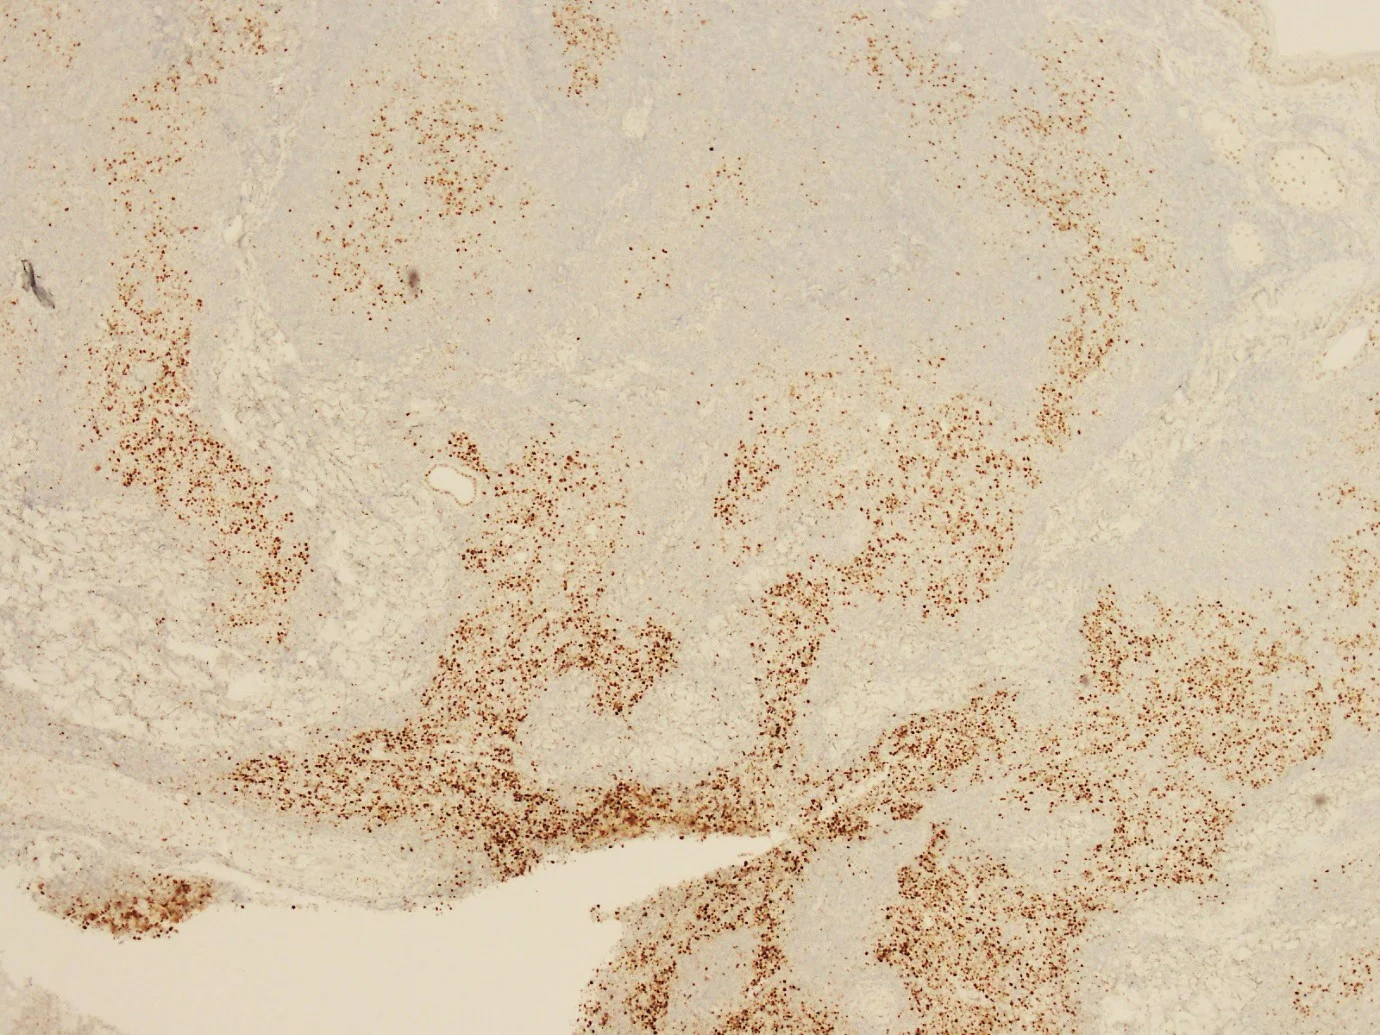

CD20

CD21

D10

BCL2

BCL6

CD79a